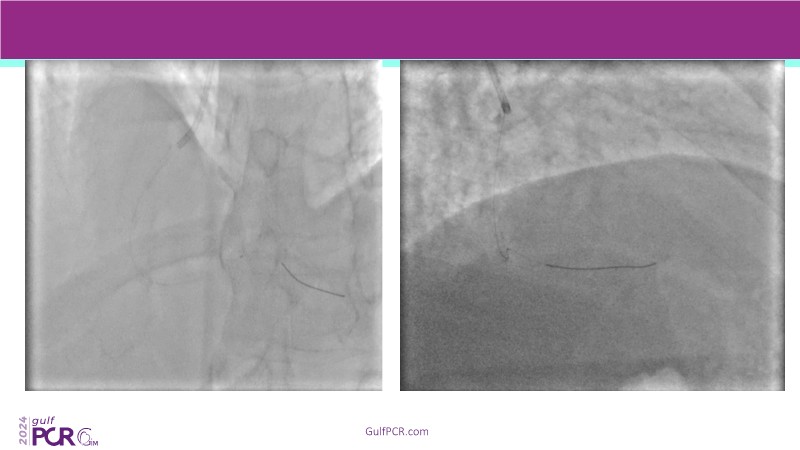

Explore cutting-edge strategies for optimizing drug-coated balloon (DCB) procedures in this session. Uncover practical tips to improve outcomes, review key indications, and examine international consensus on DCB use. Case presentations and expert discussions offer insights to refine your approach.

- To learn the tips and tricks to improve the result with drug coated balloon strategy